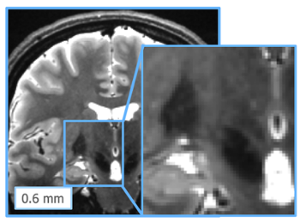

Ravi Menon was named a Fellow of the Royal Society

School of Biomedical Engineering , September 10, 2019

Ravi Menon has been elected by his peers in recognition of outstanding scholarly, scientific and artistic achievement. Election to the academies of the RSC is the highest honour a scholar can achieve in the arts, humanities and sciences.